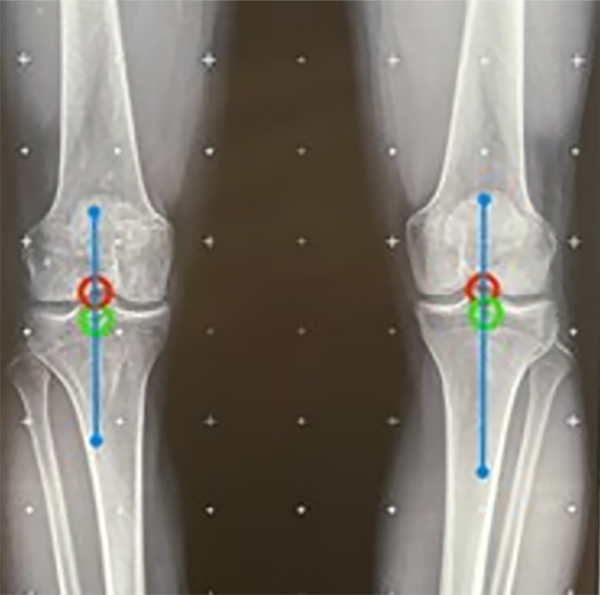

El test de mal alineamiento continúa con dos anexos: el 1 se realiza para descartar la subluxación de la articulación de la rodilla y el anexo 2 evalúa la alineación condilar.

Figura 6: Se observan el punto central de la línea de orientación articular, en rojo el de fémur distal y en verde de tibia proximal, y la línea azul muestra que el anexo de subluxación está en 0 mm (rango normal: 0-3 mm).